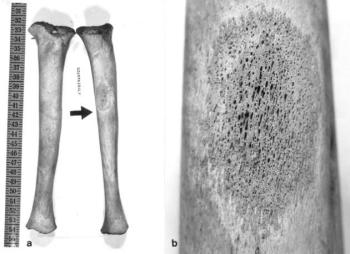

117. ábra. a) A tibia proximális harmadában osteoporosis hyperostoticara emlékeztető csontelváltozás látszik (Más csonton hasonló eltérés nem volt) b) A fenti terület kinagyított képe. 3× nagyítás

A veleszületett syphilisnek többféle kimenetele lehet. A fertőzött magzat gyakran méhen belül elhal, máskor alacsony súllyal születik, a jellegzetes tüneteket hordozza, s néhány hetes, vagy hónapos korában elpusztul. Syphilis connatalis tarda esetén az újszülött látszólag egészségesen jön világra, 2-3 éves korában jelentkeznek első tünetei, a hordó alakú, egymástól távol álló metszőfogak (Hutchinson fog), a koponya alaki eltérései, a tibia hyperostosisa, kardhüvely-szerű görbülete. Jacobi és mtsai (1992) a Barbados szigeten a vázak 10%-án ismerték fel a veleszületett megbetegedést. Connatalis syphilist diagnosztizáltunk a 16–17. század fordulóján élt, 9–10 évesen elhunyt gyermeken (Ferencz és Józsa 1992). A kocka-alakú koponyán a lapos, benyomott orrgyök feltehetően gumma, az orr csontos falának és peremének hyperostosisa a coryza syphilitica (syphilises nátha) következménye (115. ábra). A tibia rtg-képén a csontkéreg erős megvastagodása, lemezes hyperplasiája, a metaphysealis szivacsos állományban apró üregek jelezték a microgummák helyét (116. ábra, 117. ábra, 118. ábra).